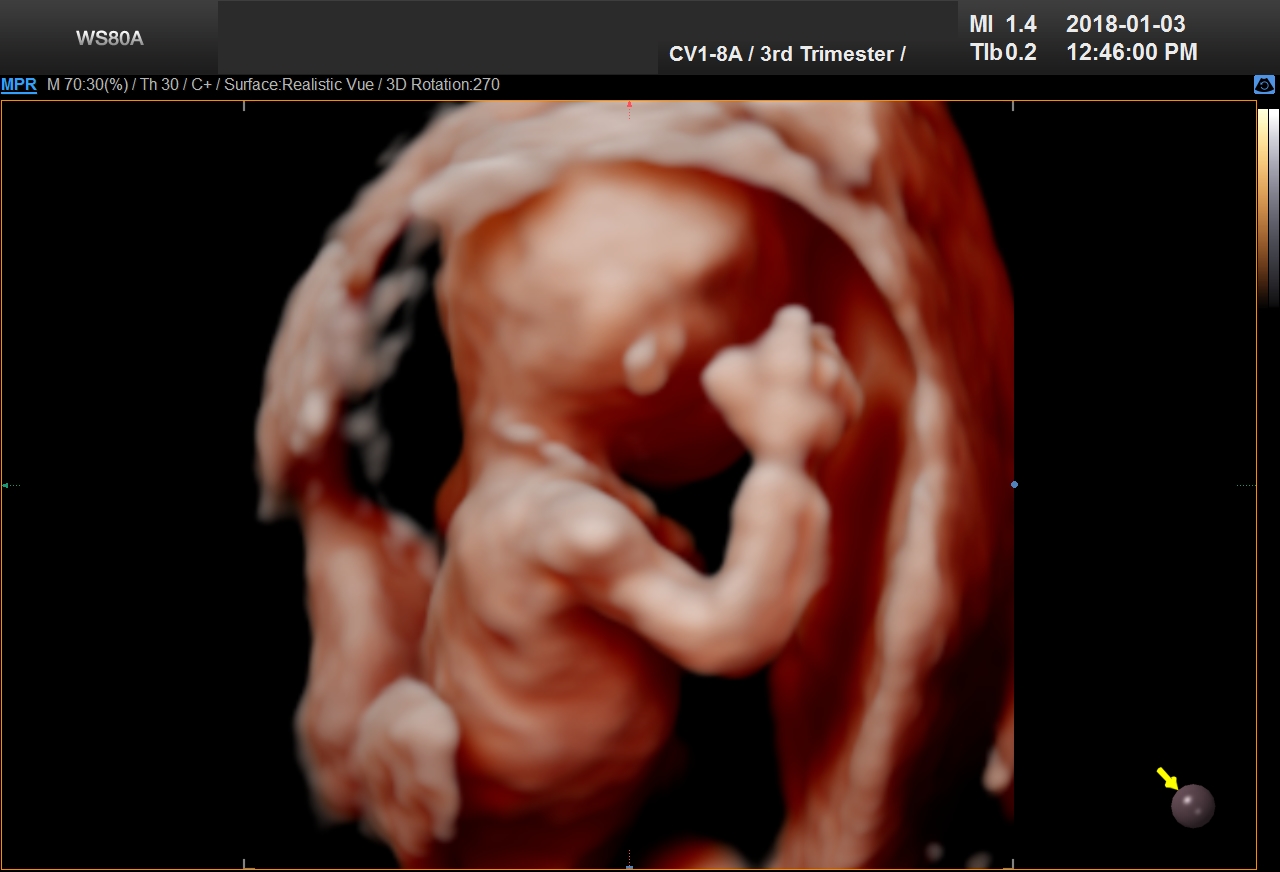

4D Ultrasound

4D Ultrasound uses 3D technology in motion, with the fourth dimension being time. This technology creates videos of the baby. Parents can watch baby’s kicks, facial expressions, yawns, and even blinking eyes with 4D scans.

5D Ultrasound

5D Ultrasound is the newest development in pregnancy imaging and it is patented by Samsung. It captures and combines high definition volume data to create automated images with amazing color and clarity. The bond between a new baby and the family gets even stronger when the family can view realistic pictures of baby in a 5D ultrasound.

UC Baby’s Latest 5D Ultrasound Service Offering

UC Baby Calgary is the first facility which brought cutting edge 5D technology to Canada. This cutting edge new ultrasound machine provides realistic pictures of the baby using the most advanced features of ultrasound imaging. We are offering high-definition 5D ultrasound technology to create unforgettable memories without extra cost. This new ultrasound technology allows families to bond stronger to the baby, with clear views of baby’s face and movements. With 5D technology, it is even possible to notice the dimples when baby smiles!

The best time to have a 5D ultrasound is between 24-32 weeks of pregnancy. Our experienced and professionally trained staff are there to amaze the mothers and their families. We also offer free online accounts for captured 2D, 3D, 4D and 5D images / videos in addition to free live broadcast of the whole ultrasound session. This is the fastest and easiest way to share baby’s first pictures and videos with friends and family instantly.